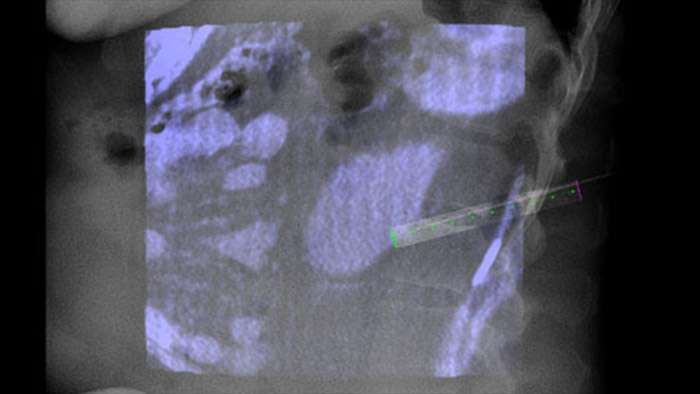

XperGuide proporciona una guía de imagen en vivo de alta precisión de cada aguja a una posición determinada mediante la superposición de trayectorias preplanificadas con imágenes fluoroscópicas.3